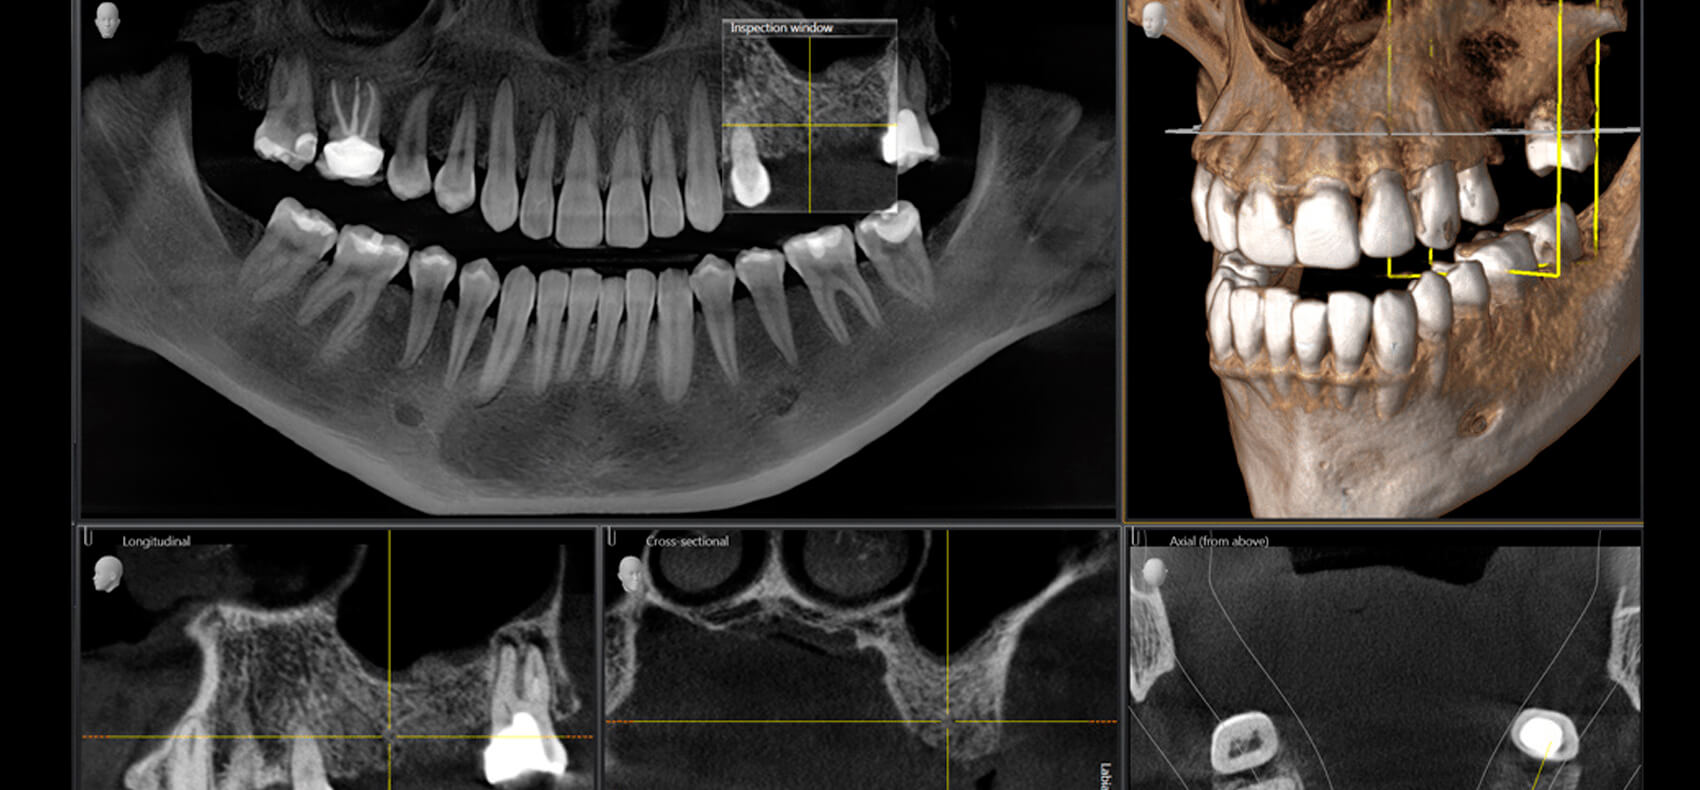

Компьютерная томография — это не просто снимок. Это объемная картина, в которой каждая структура челюсти представлена с высокой детализацией. В отличие от традиционных методов, здесь нет догадок — есть точные данные. А точность в медицине всегда равна безопасности и предсказуемости результата.

КТ позволяет врачу видеть:

- структуру костной ткани в трех измерениях

- расположение корней зубов и их анатомические особенности

- скрытые воспалительные процессы

- состояние гайморовых пазух

- точное положение нервных каналов

Такой уровень детализации исключает ошибки. Решения принимаются не на основе опыта и предположений, а на основе объективных данных.

Компьютерная томография работает иначе. Она формирует объемную модель, которую можно рассматривать под любым углом. Это принципиально иной уровень информации.

- КТ — точный, объемный, максимально информативный